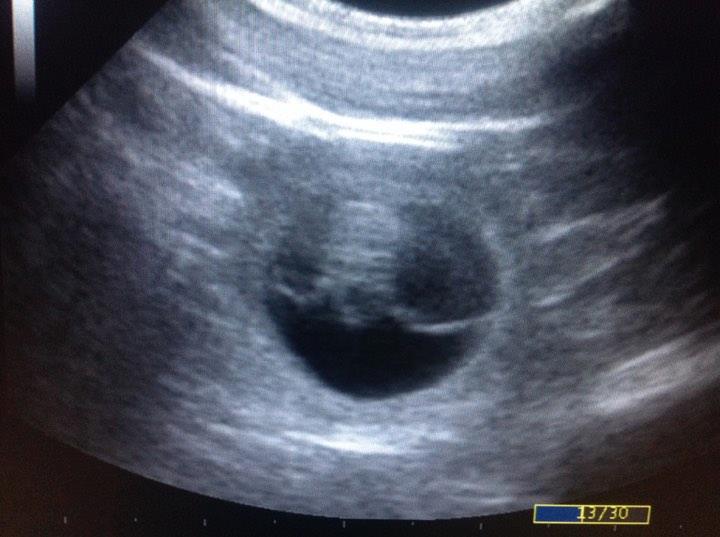

USG (sono) |

25. dňa |

sono prístrojom – vidno: plodový vačok, srdce, embryo, stena maternice. |